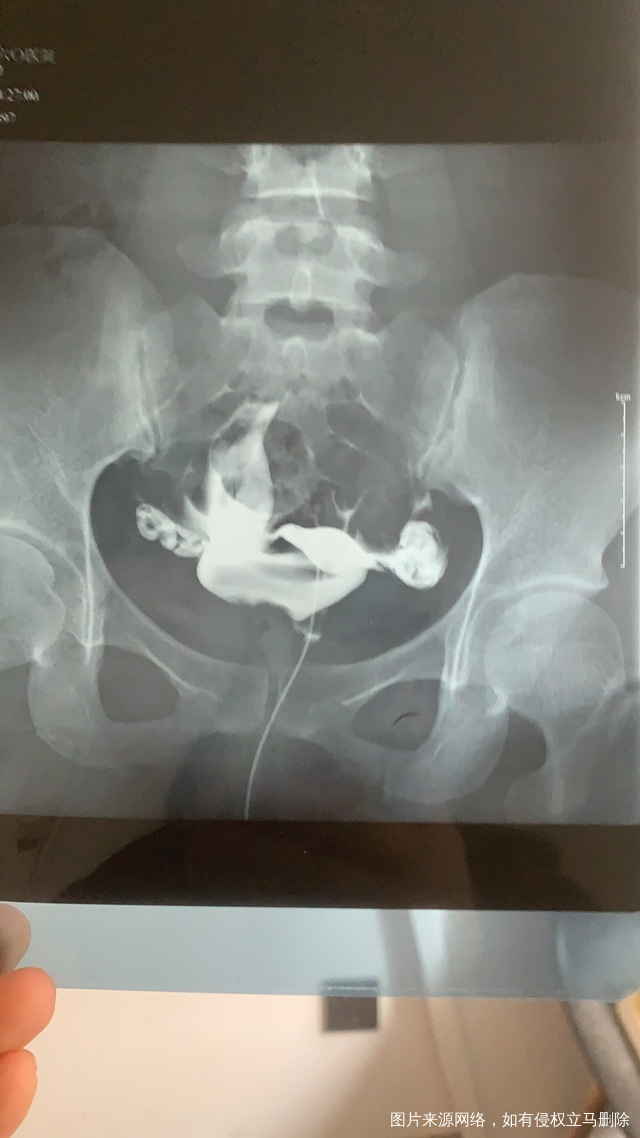

这个手术不是非得要马上做,需要根据你的年龄、生育计划等来综合评估并权衡利弊后再决定是否需要手术以及什么时候做。如果是做试管通常为了避免输卵管积液及炎症因子逆流至宫腔影响胚胎着床等,会行输卵管结扎等手术,这个手术通常在移植前完成